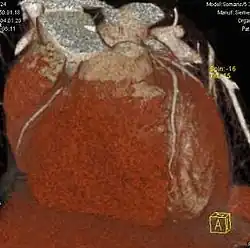

Multiplanare Reformation und 3D-Darstellungen

Erst mit der Einführung von Mehrzeilen-Spiral-CTs Mitte der 1990er Jahre gab es in der Computertomographie isotrope Voxel.[1] Da alle heutigen (2011) klinischen CTs kleine isotrope Voxel erzeugen können, ist eine hohe räumliche Auflösung in beliebigen Raumrichtungen möglich. Durch die multiplanare Reformation werden auch sagittale und koronale Darstellungen in hoher Qualität möglich, die für den Nicht-Radiologen erheblich einfacher zu verstehen sind. Die Maximum Intensitäts Projektion stellt die Maximalwerte aus einem frei wählbaren Datenvolumen dar, die auf eine Ebene projiziert werden, vergleichbar einem Schattenbild. Durch die heute auf Auswerte- bzw. PACS-Workstations preiswert verfügbare Rechenleistung können aus den Daten auch hochwertige 3D-Darstellungen in Form von MIP, Surface-Rendering oder – am aufwändigsten und beeindruckendsten – Raycasting erzeugt werden.

Für den Radiologen in der klinischen Routine ist die MIP zur Gefäßdarstellung und der Suche nach Lungenmetastasen sehr hilfreich. Eine 3D-Darstellung ist zur präoperativen Darstellung von Mehrfragment-Frakturen für den Chirurgen nützlich. Raytracing und MIP werden ferner im Rahmen von Spezialanwendungen für Visualisierungen in der Computertomographie des Herzens und der virtuellen Koloskopie verwendet.